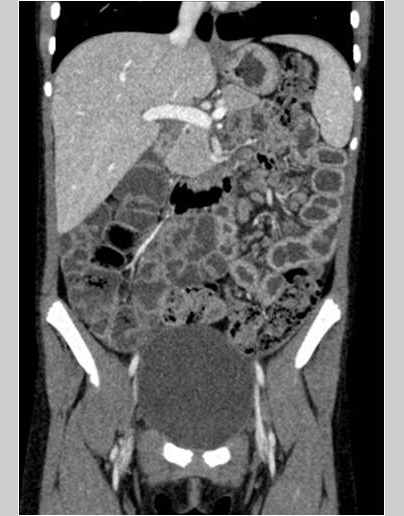

Se aprecian cuatro lesiones hipodensas en el bazo. En los cortes coronales se aprecia hipercaptación mucosa en las asas del yeyuno, adenopatías de tamaño patológico, aumento de la vascularización del meso y líquido libre en la fosa iliaca derecha.

• Hipercaptación mucosa en las asas del yeyuno, con adenopatías regionales de tamaño patológico y aumento de vascularización en el meso.

• Discreta cantidad de líquido libre en fosa iliaca derecha.